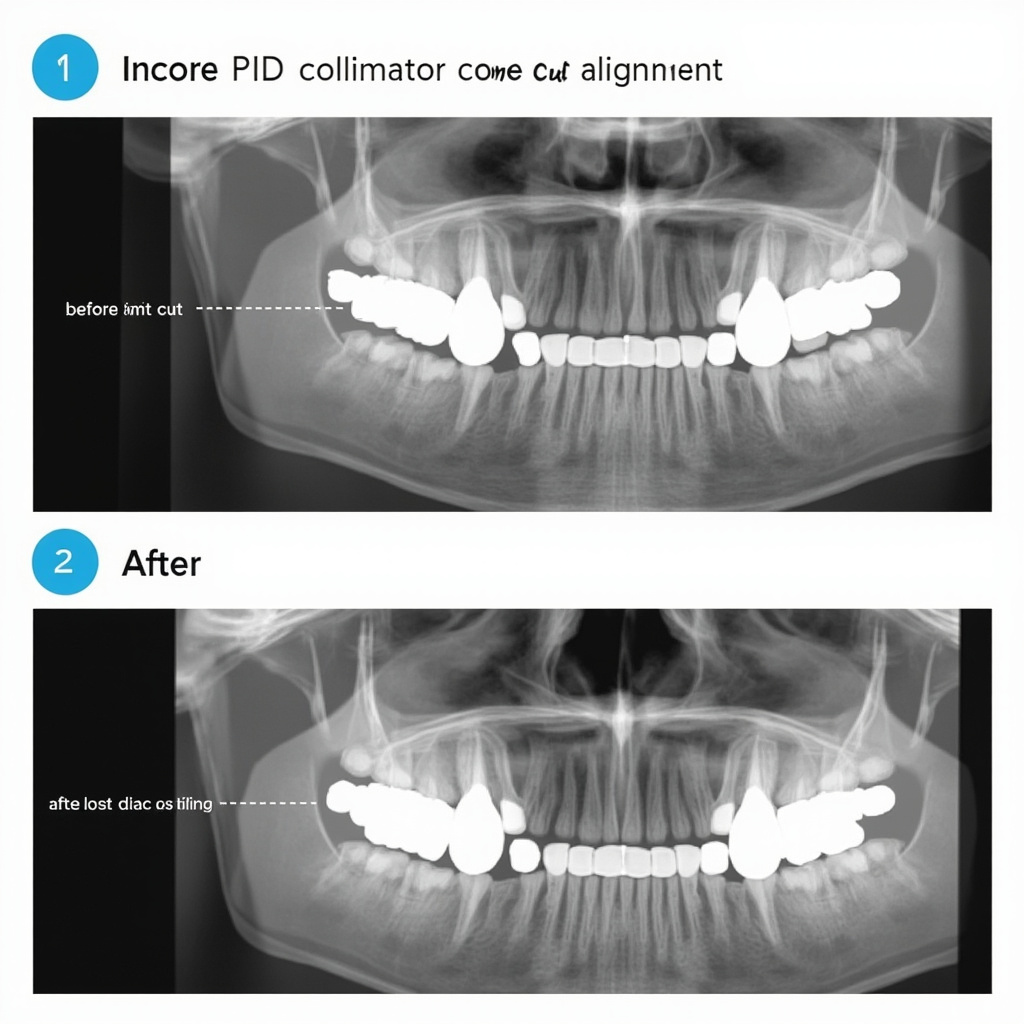

- Inconsistent Image Density: Images appear too light or dark despite consistent exposure settings

- Exposure Timer Inaccuracy: Actual exposure times deviate from programmed values

Dental X-ray systems are particularly sensitive to power fluctuations because they rely on precise voltage control for exposure parameter accuracy. When input voltage varies, the resulting kVp and mAs settings can deviate from intended values, directly affecting image quality and patient radiation dose.